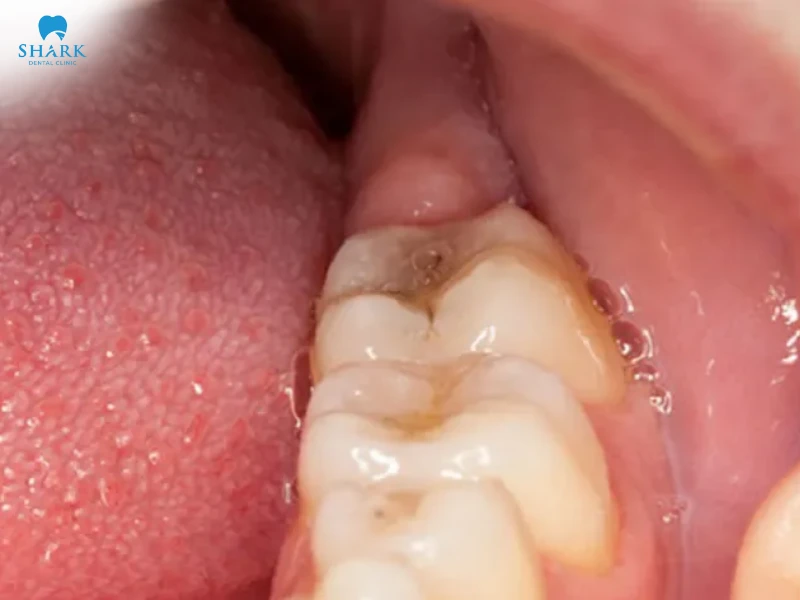

Lợi trùm răng khôn thực chất là quá trình khi răng khôn mọc lên xuất hiện dấu hiệu sưng tấy, có phần lợi bao trùm che phủ hết bề mặt của răng. Khi răng mọc sẽ đâm lên phần lợi, gây hiện tượng sưng viêm, đau nhức, ảnh hưởng đến quá trình ăn nhai.

- Lợi bị sưng đỏ ngay chính giữa răng khôn. Phần lợi trùm và bao bọc xung quanh răng khôn

- Lợi sưng tấy, có mưng mủ, chảy máu và đau nhức

- Lợi trùm răng khôn gây sốt cao, khó chịu, tác động đến quá trình vệ sinh và ăn nhai

- Miệng bị hôi do răng khôn bị lợi trùm viêm nhiễm, vi khuẩn tích tụ nhiều dưới chân răng.